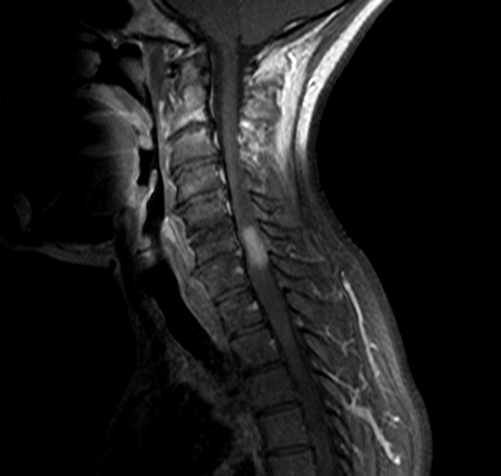

MRI of the cervical and thoracic spine showed a diffuse, intramedullary abnormal signal extending from the medulla down to approximately the mid-thoracic level. There was swelling in portions of the spinal cord, particularly in the lower cervical cord where there was contrast enhancement (Figure 1 [Fig. 1], Figure 2 [Fig. 2], Attachment 1 [Att. 1]). The MRI of the brain was normal.

Figure 1: MRI of the cervical spine, sagittal view: contrast enhancement in the lower cervical cord